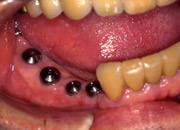

・CASE.2(下顎に 4 本のインプラントを埋入した症例)

まず、インプラントを埋入し仮のブリッジを装着します。この状態でも通常通りに生活ができます。 |

顎骨と結合するのを待ち、最終的なブリッジを装着します。通常インプラント埋入から1〜2ヶ月後に行います。 |